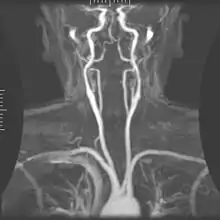

Angiography

Magnetic resonance angiography (MRA) generates pictures of the arteries to evaluate them for stenosis (abnormal narrowing) or aneurysms (vessel wall dilatations, at risk of rupture). MRA is often used to evaluate the arteries of the neck and brain, the thoracic and abdominal aorta, the renal arteries, and the legs (called a "run-off"). A variety of techniques can be used to generate the pictures, such as administration of a paramagnetic contrast agent (gadolinium) or using a technique known as "flow-related enhancement" (e.g., 2D and 3D time-of-flight sequences), where most of the signal on an image is due to blood that recently moved into that plane (see also FLASH MRI).[39]

Techniques involving phase accumulation (known as phase contrast angiography) can also be used to generate flow velocity maps easily and accurately. Magnetic resonance venography (MRV) is a similar procedure that is used to image veins. In this method, the tissue is now excited inferiorly, while the signal is gathered in the plane immediately superior to the excitation plane—thus imaging the venous blood that recently moved from the excited plane.[40]